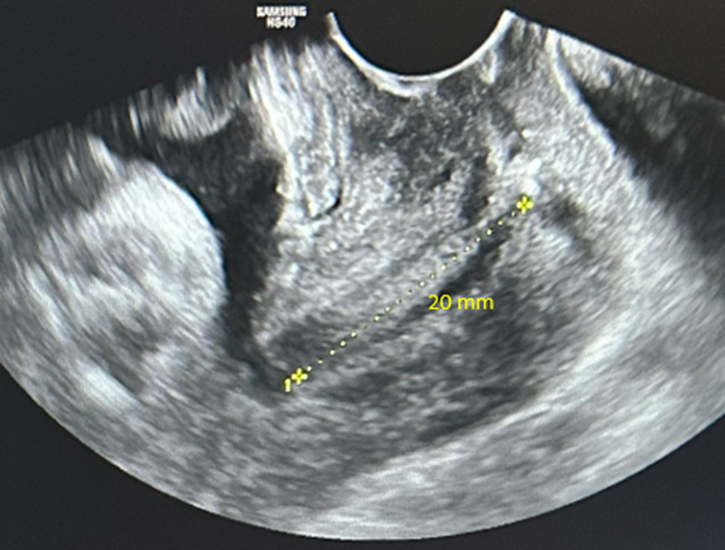

Il existe une franche cassure de la courbe, le fœtus est passé au troisième percentile. L’échographie en figure 1 est un écho-Doppler de l’artère ombilicale. Elle montre une diastole ombilicale nulle. Il s’agit donc d’un RCIU et non d’un fœtus petit pour l’âge gestationnel.

Concernant l’échographie de vitalité fœtale (figure 3), elle décrit :

– l’analyse du Doppler de l’artère ombilicale qui témoigne des échanges entre le fœtus et la mère (par ordre de gravité : diastole ombilicale positive normale ; diastole ombilicale nulle ; reverse-flow) ;